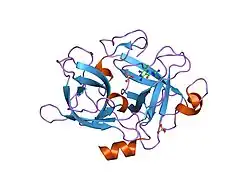

Urokinase is a 411-residue protein, consisting of three domains: the serine protease domain (consisting of residues 159–411), the kringle domain (consisting of residues 50-131), and the EGF-like domain (consisting of residues 1-49). The kringle domain and the serine protease domain are connected by an interdomain linker or connecting peptide (consisting of residues 132–158). Urokinase is synthesized as a zymogen form (prourokinase or single-chain urokinase), and is activated by proteolytic cleavage between Lys158 and Ile159. The two resulting chains are kept together by a disulfide bond between Cys148 and Cys279.[9]